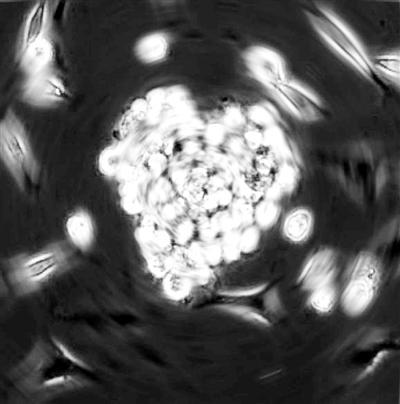

左图 在显微照片中,从小鼠心脏分离的心脏干细胞聚集成心脏的形状。